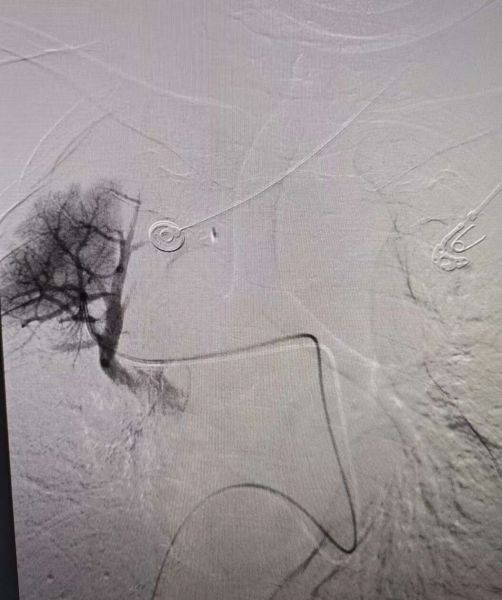

右肺动脉术后造影:闭塞血管开通

右肺动脉血管开通仍见较大血栓影